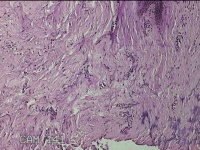

右下腹部切口结节

性别

女

年龄

27岁

临床诊断

皮下结节

一般病史

发现右下腹部切口结节10余年。

标本名称

大体所见

灰白暗红色带皮肤样结节2.3x1.3x0.8cm一个。表面糜烂,切面灰白色,质硬。

需要侵袭性纤维瘤病和纤维瘢痕鉴别一下